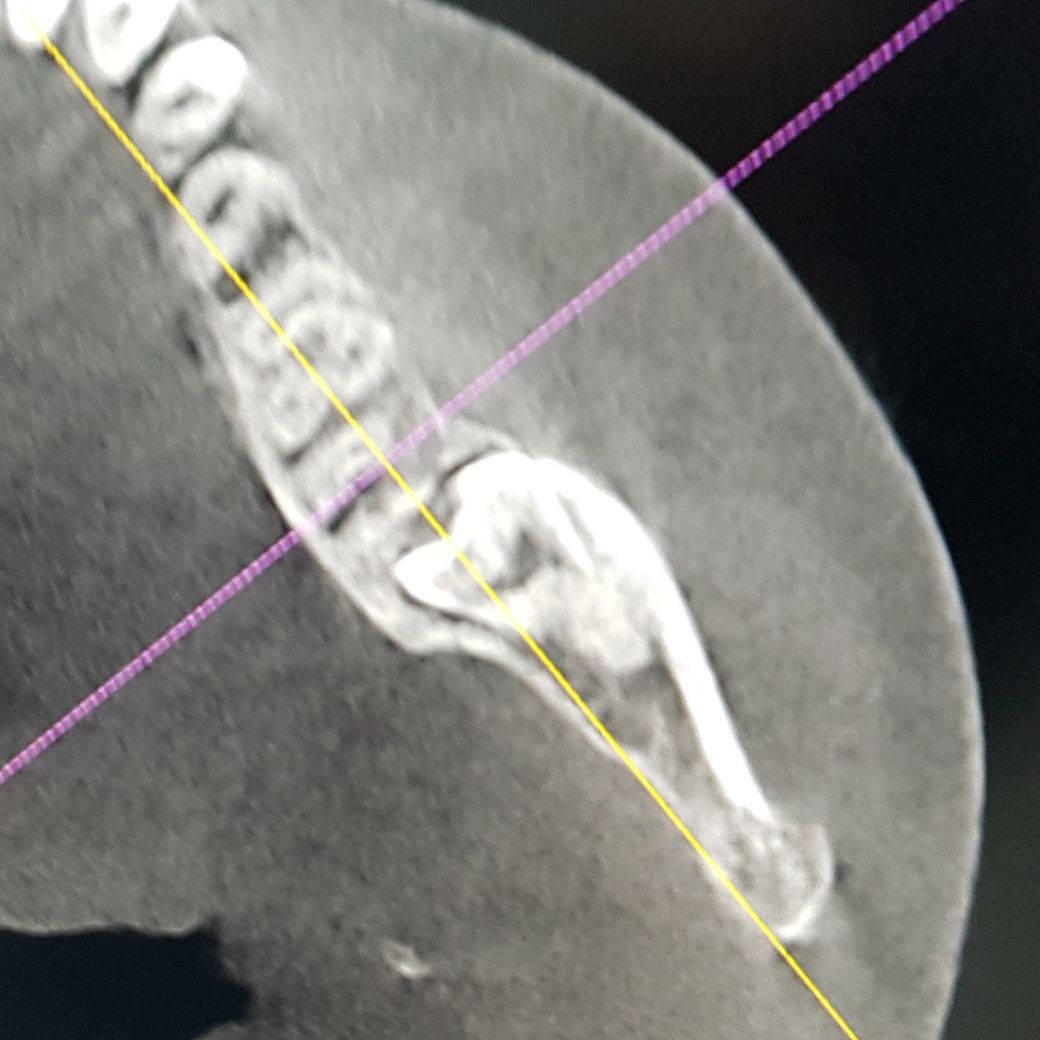

사진과 같이 매복 사랑니 때문에 앞 어금니 뿌리가 먹혔다는 진단을 받아서 둘 다 한꺼번에 발치할 예정입니다. 아무래도 임플란트를 하는 수밖에 없을까요? 혹시 다른 방법이 있을지 궁금해서 여쭤봅니다.

• 1번 째 사진

• 2번 째 사진

• 3번 째 사진